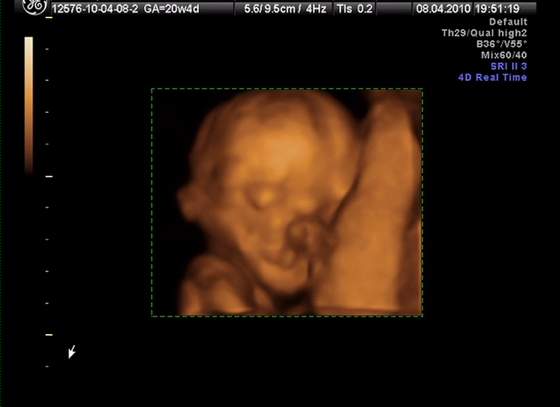

śliczna panienka rośnie :-)Przyszła kolej na moją śliczną córunię - mam nadzieję, że już jej nic nie wyrośnie, bo się przyzwyczaiłam... :-)

kolejno: uśmiech, pipulka, twarzyczka i krągła dupcia